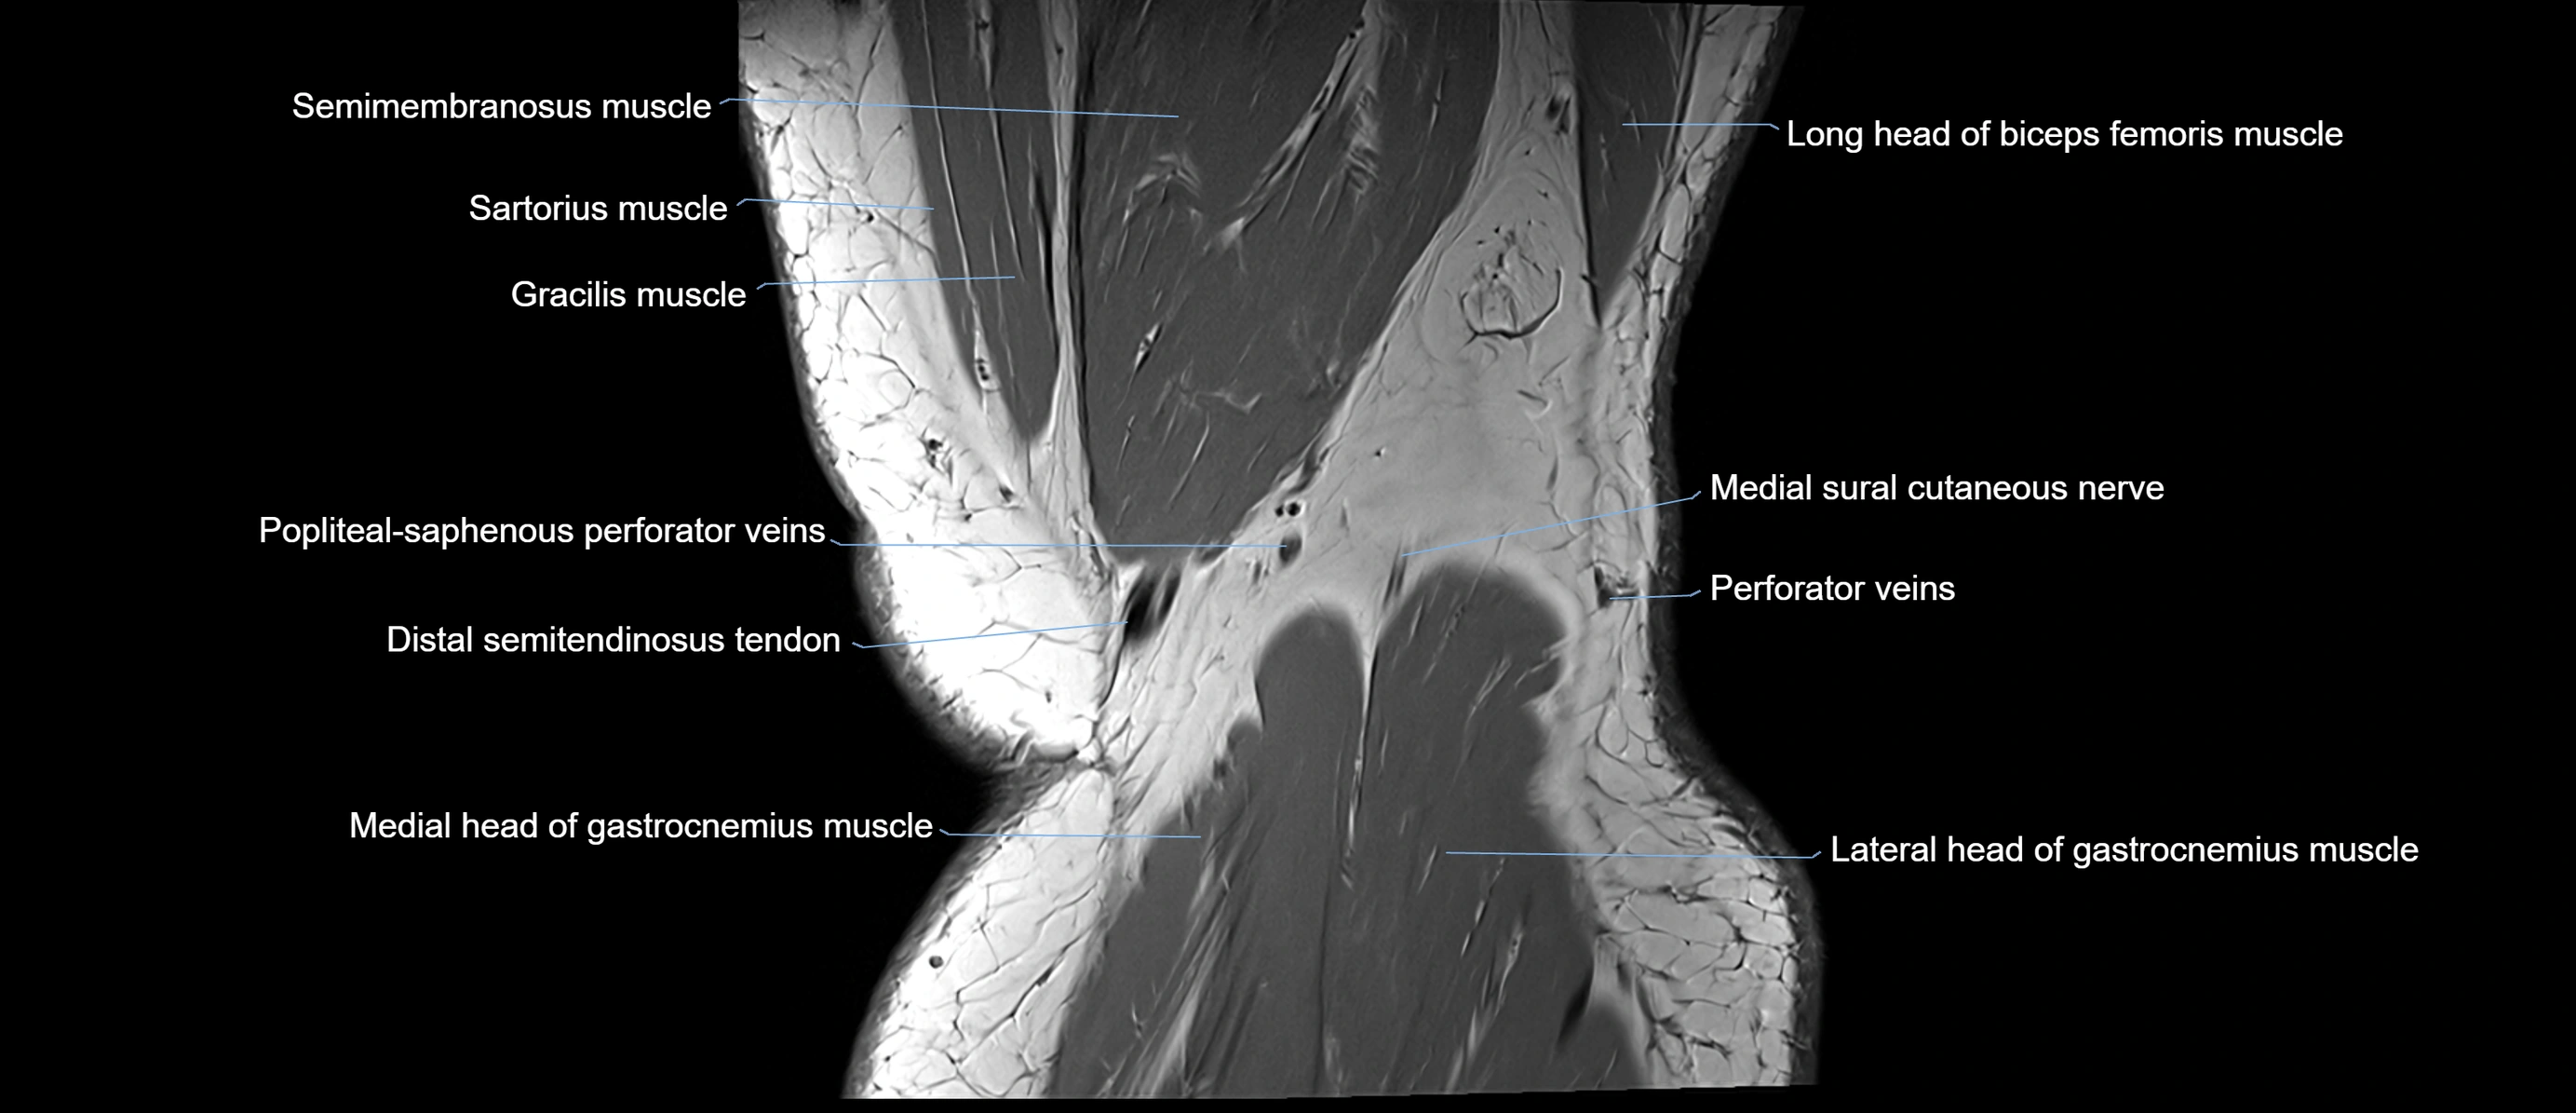

- Medial head of gastrocnemius muscle

- Lateral head of gastrocnemius muscle

- Medial sural cutaneous nerve

- Popliteal–Saphenous perforating veins

- Distal semitendinosus tendon

- Sartorius muscle

- Semimembranosus muscle

- Biceps femoris muscle (Long head)